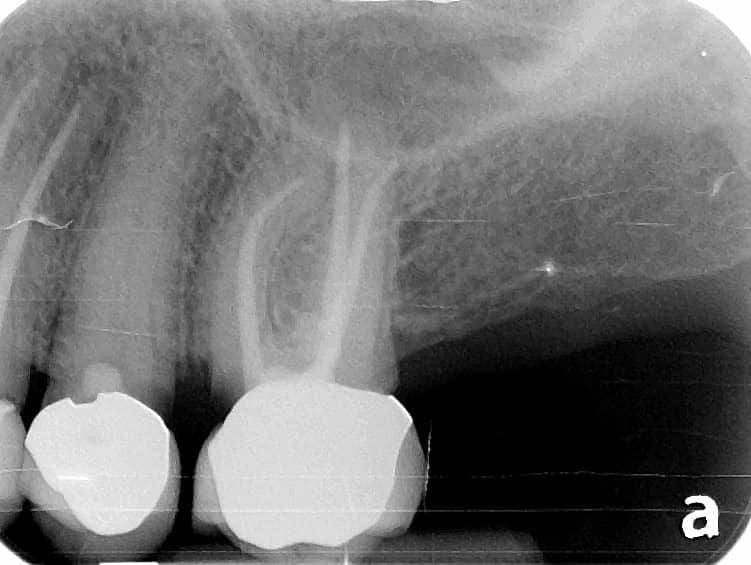

Below is a case of full arch same day temporization using the socket shield , root submergence and pontic shield techniques to preserve the site architecture . Neodent GM implants were placed in a guided fashion and same day temporization was performed using a milled PMMA.